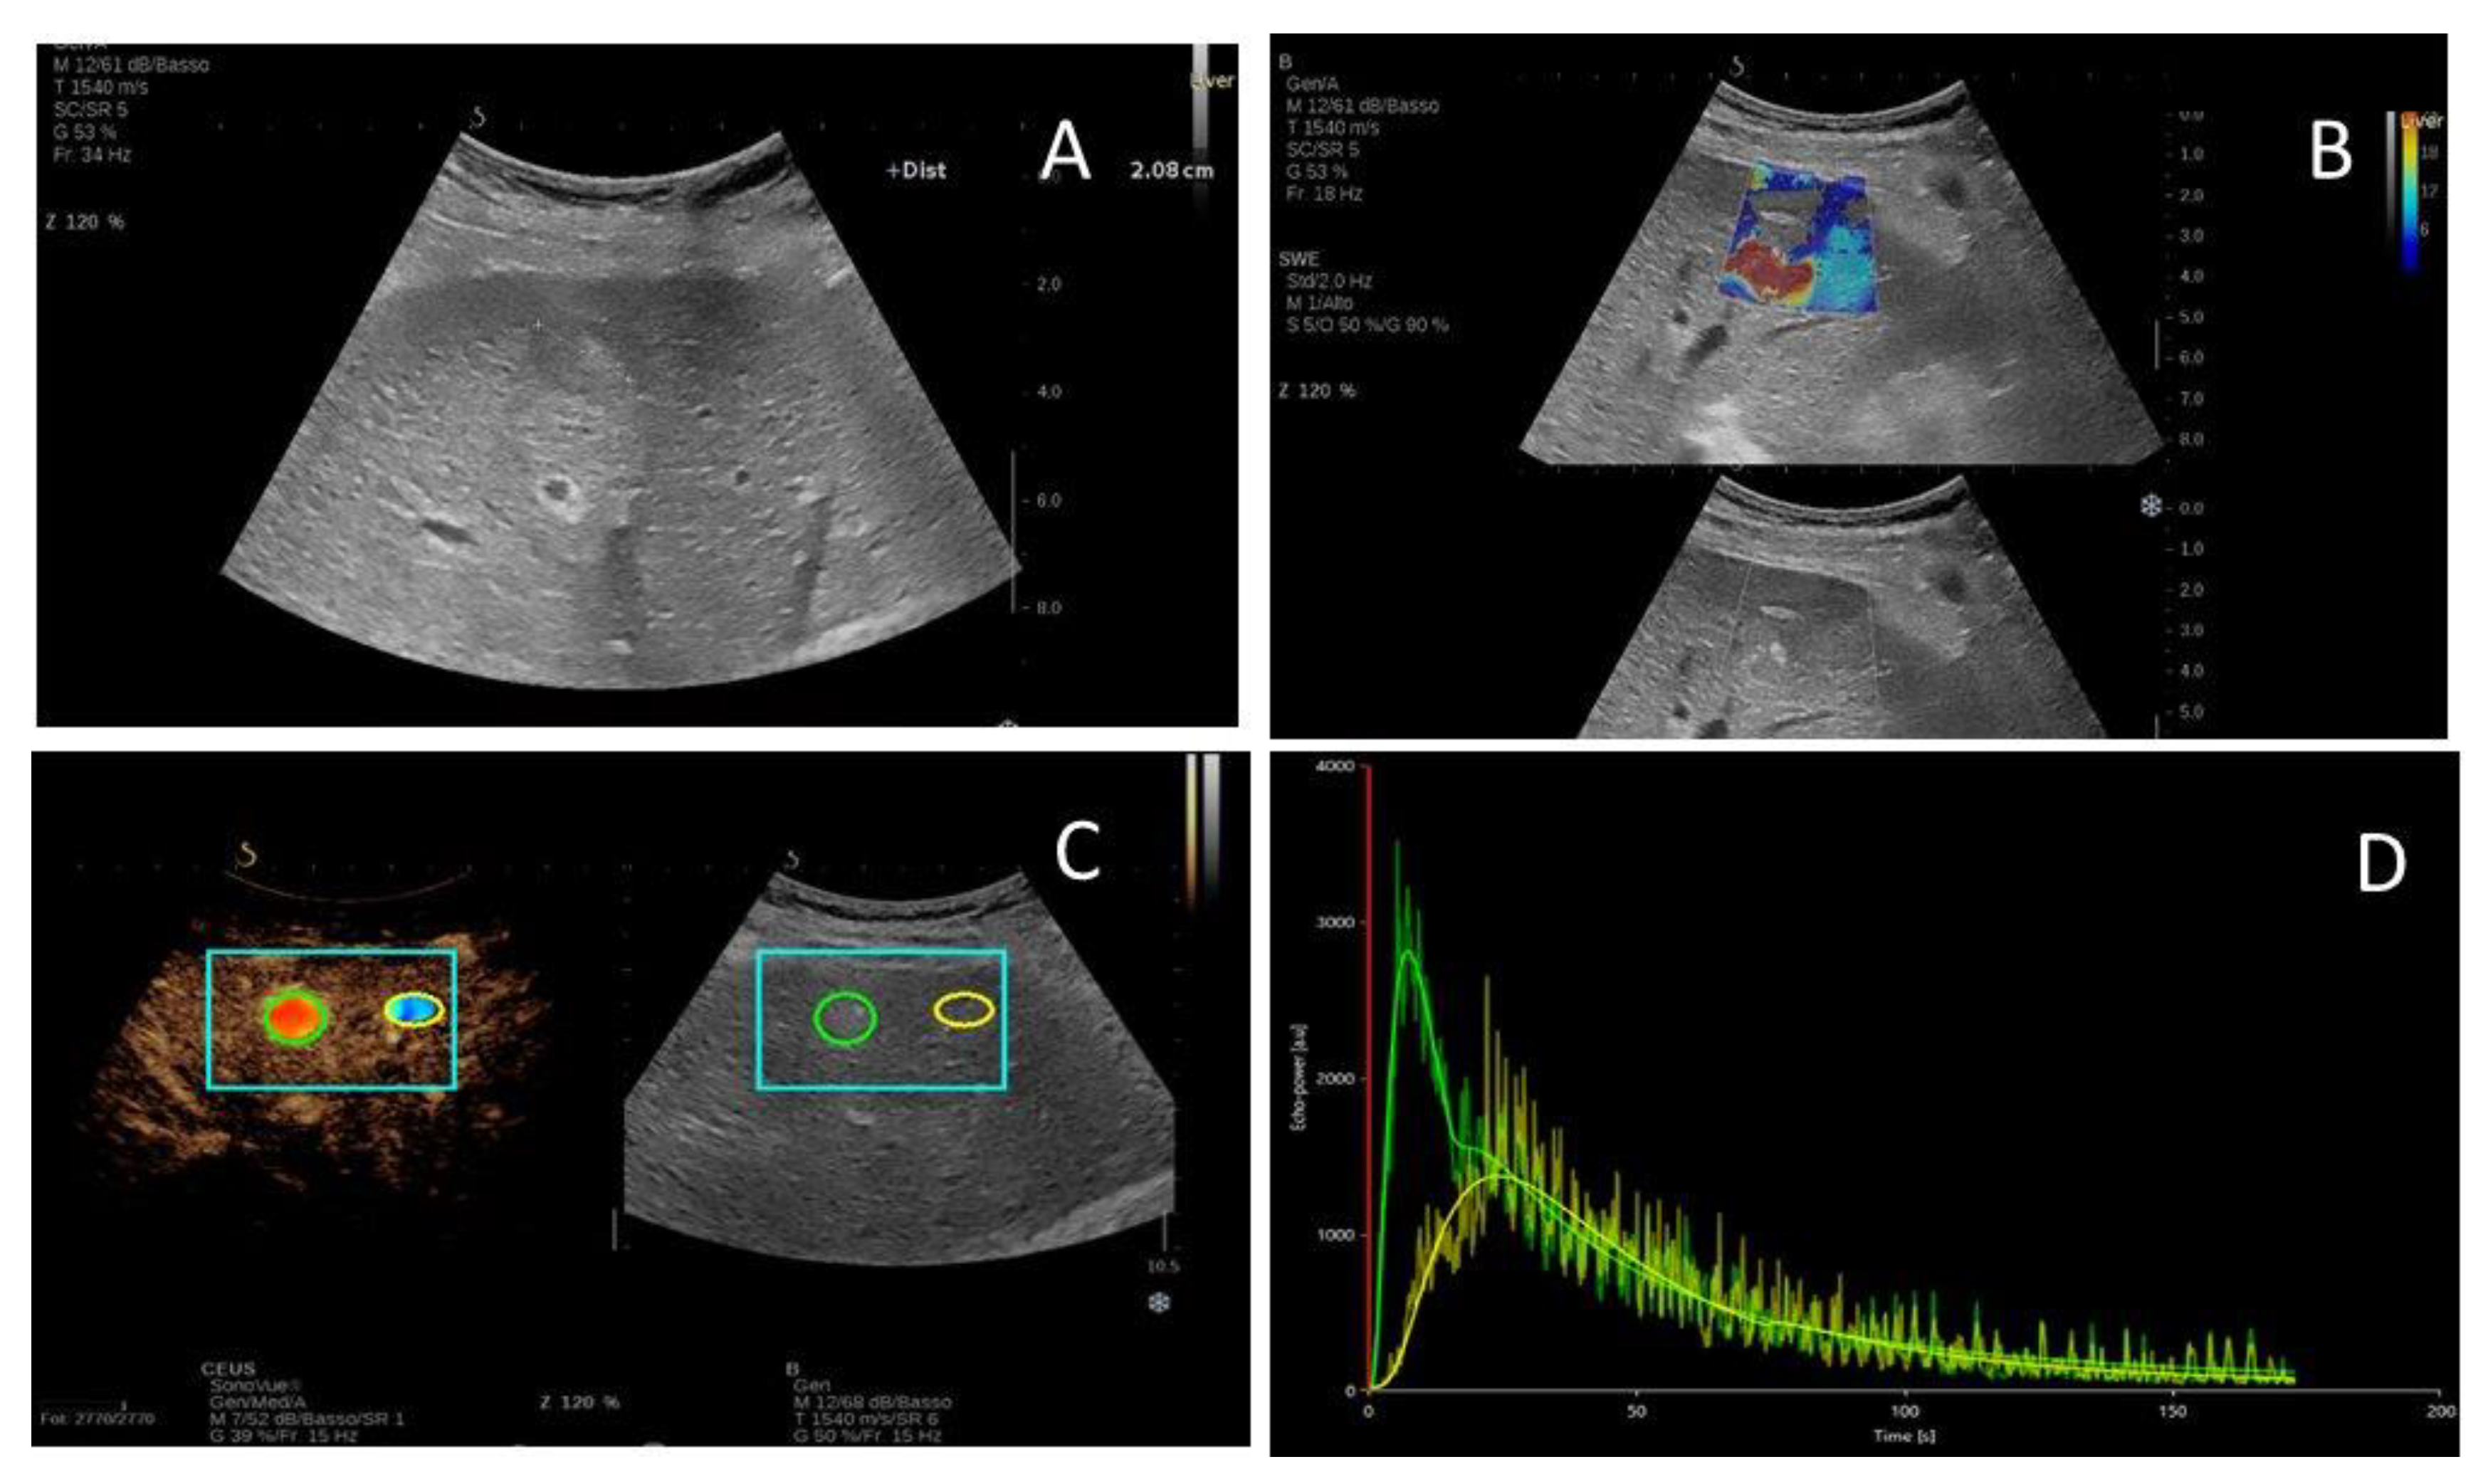

2.2. US Imaging Characteristics